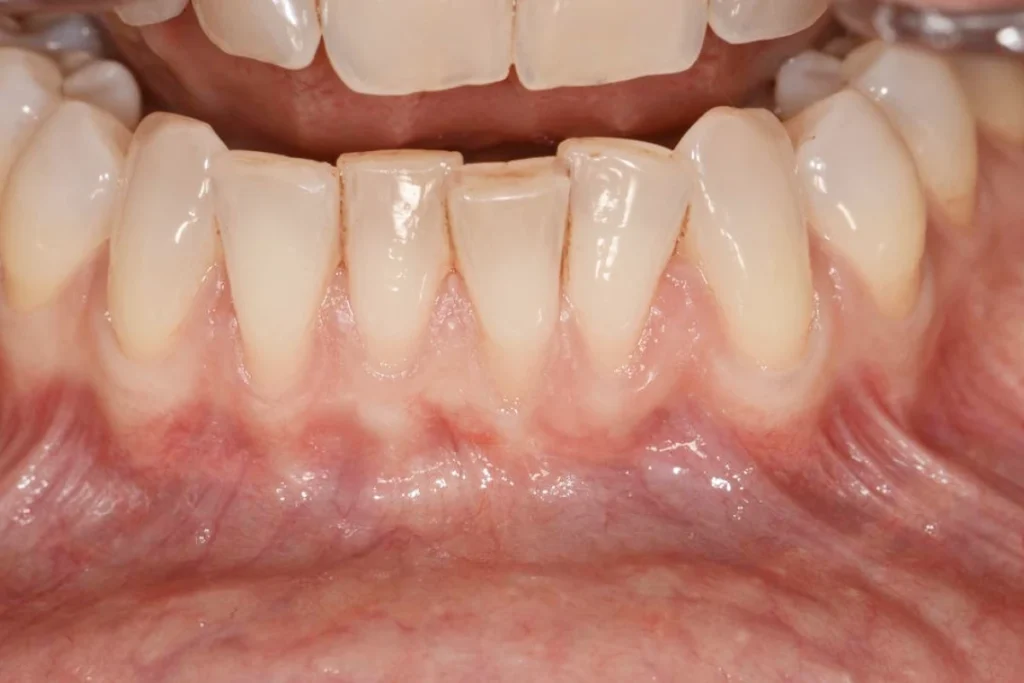

La greffe gingivale à visée esthétique est indiquée en cas de déchaussement d’une ou plusieurs racines dentaires visibles lors du sourire. Le patient consulte car il trouve ses dents plus longues et son sourire disharmonieux.

Le déchaussement peut également être à l’origine de sensibilités dentaires au chaud ou au froid car l’émail n’est pas présent sur la partie de la racine qui n’est plus recouverte de gencive. La greffe de gencive va permettre dans ces cas-là de remettre de la gencive dans la ou les zones où elle fait défaut.

Dans les 2 types de greffes le prélèvement est fait au niveau du palais du patient. Pas de rejet possible ou de problème d’allergie!